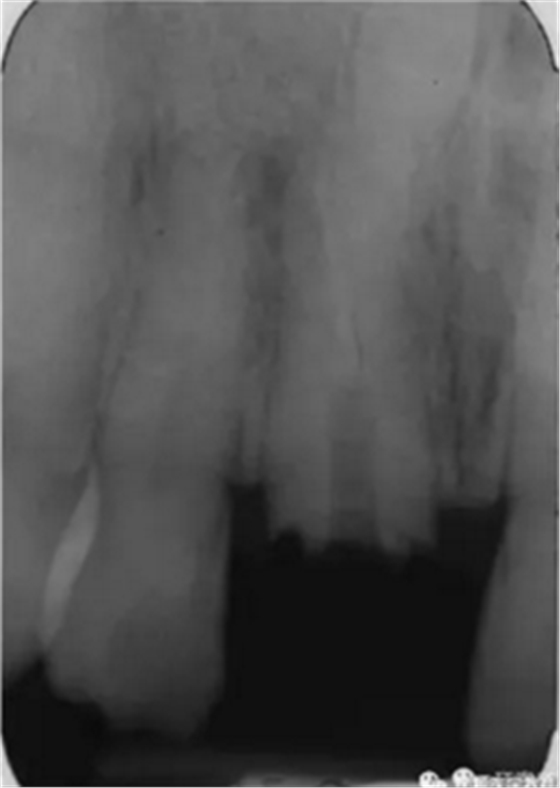

本例患者為男性,53歲,由于右上頜中切牙疼痛,在蘇格蘭的格拉斯哥口腔醫(yī)院就診。根管治療后1年來(lái)牙齒出現(xiàn)自發(fā)性疼痛。檢查發(fā)現(xiàn)患者冠部修復(fù)體3周前丟失,未發(fā)現(xiàn)竇道,牙面較多部位探診時(shí)患者較敏感,說(shuō)明牙齒仍為活髓,可以修復(fù)。患者身體狀況良好。影像學(xué)顯示,患牙根尖彎曲處充填不充分,根尖周有陰影,還發(fā)現(xiàn)在右上頜中切牙的根尖部有一倒置的額外牙顯影,周?chē)乐苣挾日!?/p>

圖1. 治療前患牙根尖周顯影